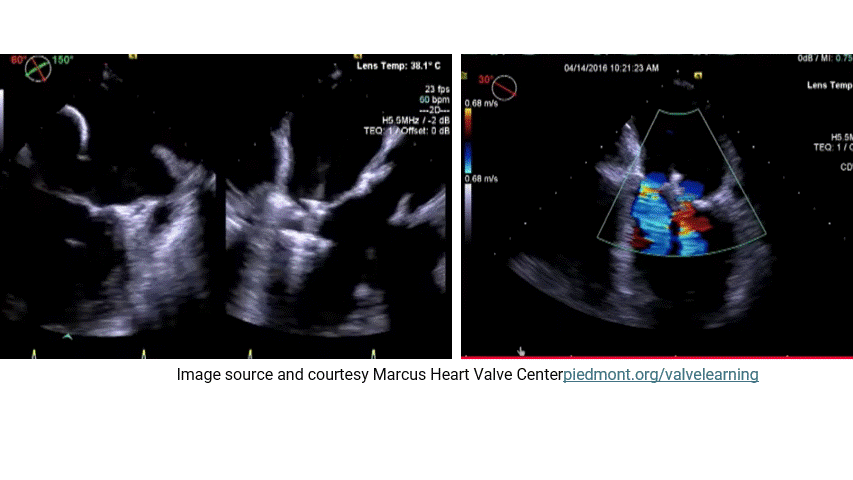

The MitraClip procedure, is designed to reduce mitral regurgitation (MR) by approximating the mitral valve leaflets, can alter the direction or nature of residual MR, including potentially converting a central MR jet into an eccentric one . This possiblity depends on the pre-procedural anatomy, the placement of the clips, and the resulting changes in mitral valve dynamics.

Central MR in ischemic dilated cardiomyopathy (DCM) typically arises from functional MR, where symmetric annular dilation and leaflet tethering (due to LV remodeling) create a central regurgitant jet through a malcoapted valve. The MitraClip works by grasping the anterior and posterior leaflets, usually at the A2-P2 segments, to create a double-orifice valve, reducing the regurgitant orifice area. When successful, this diminishes the overall MR volume, often preserving the jet’s central nature if residual MR remains.

However, if the clip placement is asymmetri or if multiple clips are positioned unevenly, the geometry of the mitral valve can shift. This could redirect the residual regurgitant flow. For example, if the clip is placed more toward the medial or lateral commissure, or if it disproportionately restricts one leaflet’s motion (e.g., excessive tethering of the posterior leaflet), the remaining gap might produce an eccentric jet directed toward the opposite side of the left atrium.

Echocardiographic studies post-MitraClip occasionally report changes in jet direction. While the primary goal is MR reduction, not all procedures eliminate regurgitation entirely, and residual MR jets can appear eccentric depending on how the leaflets coapt after clipping. For instance, if the clip reduces central coaptation but leaves a smaller, off-center orifice, the jet might angle toward the atrial wall, resembling eccentric MR seen in organic valve disease (e.g., prolapse). This isn’t necessarily a conversion from central to eccentric in the classical sense but rather a modification of the residual flow pattern.